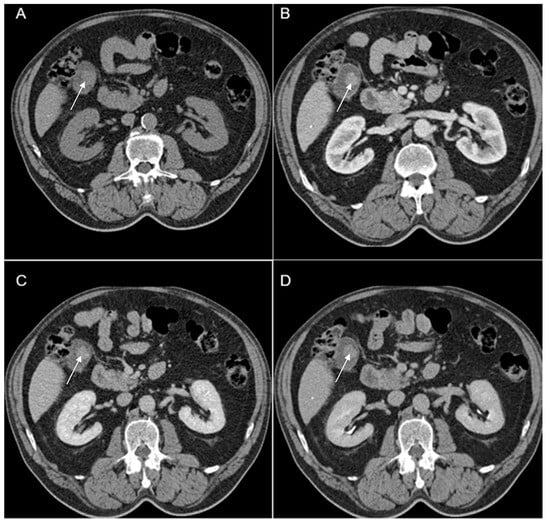

Figure 7. Multiplanar sections of contrast-enhanced CT acquisitions richly illustrating gallbladder carcinoma. (AD). Heterogeneous, contrast-enhancing intraluminal gallbladder mass located in the gallbladder fundus region (black star).

A 63-year-old man with a history of severe hyponatremia, known prostate adenocarcinoma and gastroduodenal ulcer with Billroth I gastric resection presented with nausea, vomiting, dizziness and weight loss for one month. On physical examination, abdominal tenderness was noted. Routine laboratory evaluation demonstrated normal leukocytes and inflammatory markers, moderate anemia and severe hyponatremia (serum sodium was 108 mmol/L). Contrast-enhanced CT (Figure 7) showed a heterogeneous intraluminal gallbladder mass, measuring 25/24/35 mm, localized in gallbladder fundus (Panel A, Panel B, Panel C and Panel D). The mass had no invasion of the adjacent structures and no associated imaging findings. An abdominal MRI was performed (Figure 8).

Furthermore, a laparoscopic cholecystectomy was performed. The histopathological exam revealed gallbladder carcinoma.

The particularity of this case report is amply illustrated by severe hyponatremia presented as paraneoplastic SIADH syndrome (syndrome of inappropriate antidiuretic hormone secretion) in a patient with gallbladder carcinoma.

In our Case 5 report (Figure 7), the patient presented gallbladder carcinoma with endocrine manifestation. Gallbladder cancer associated with SIADH syndrome represents a very rare entity with few cases reported in the current literature. Hyponatremia (<135 mmol/L) is correlated with a negative prognosis and in some case is a predictive factor for cancer patients. Paraneoplastic syndrome of inappropriate antidiuretic hormone secretion (SIADH) is induced by the abnormal secretion of antidiuretic hormone by tumoral cells [21]. In our case, the final diagnosis was gallbladder carcinoma associated with SIADH as a paraneoplastic syndrome.